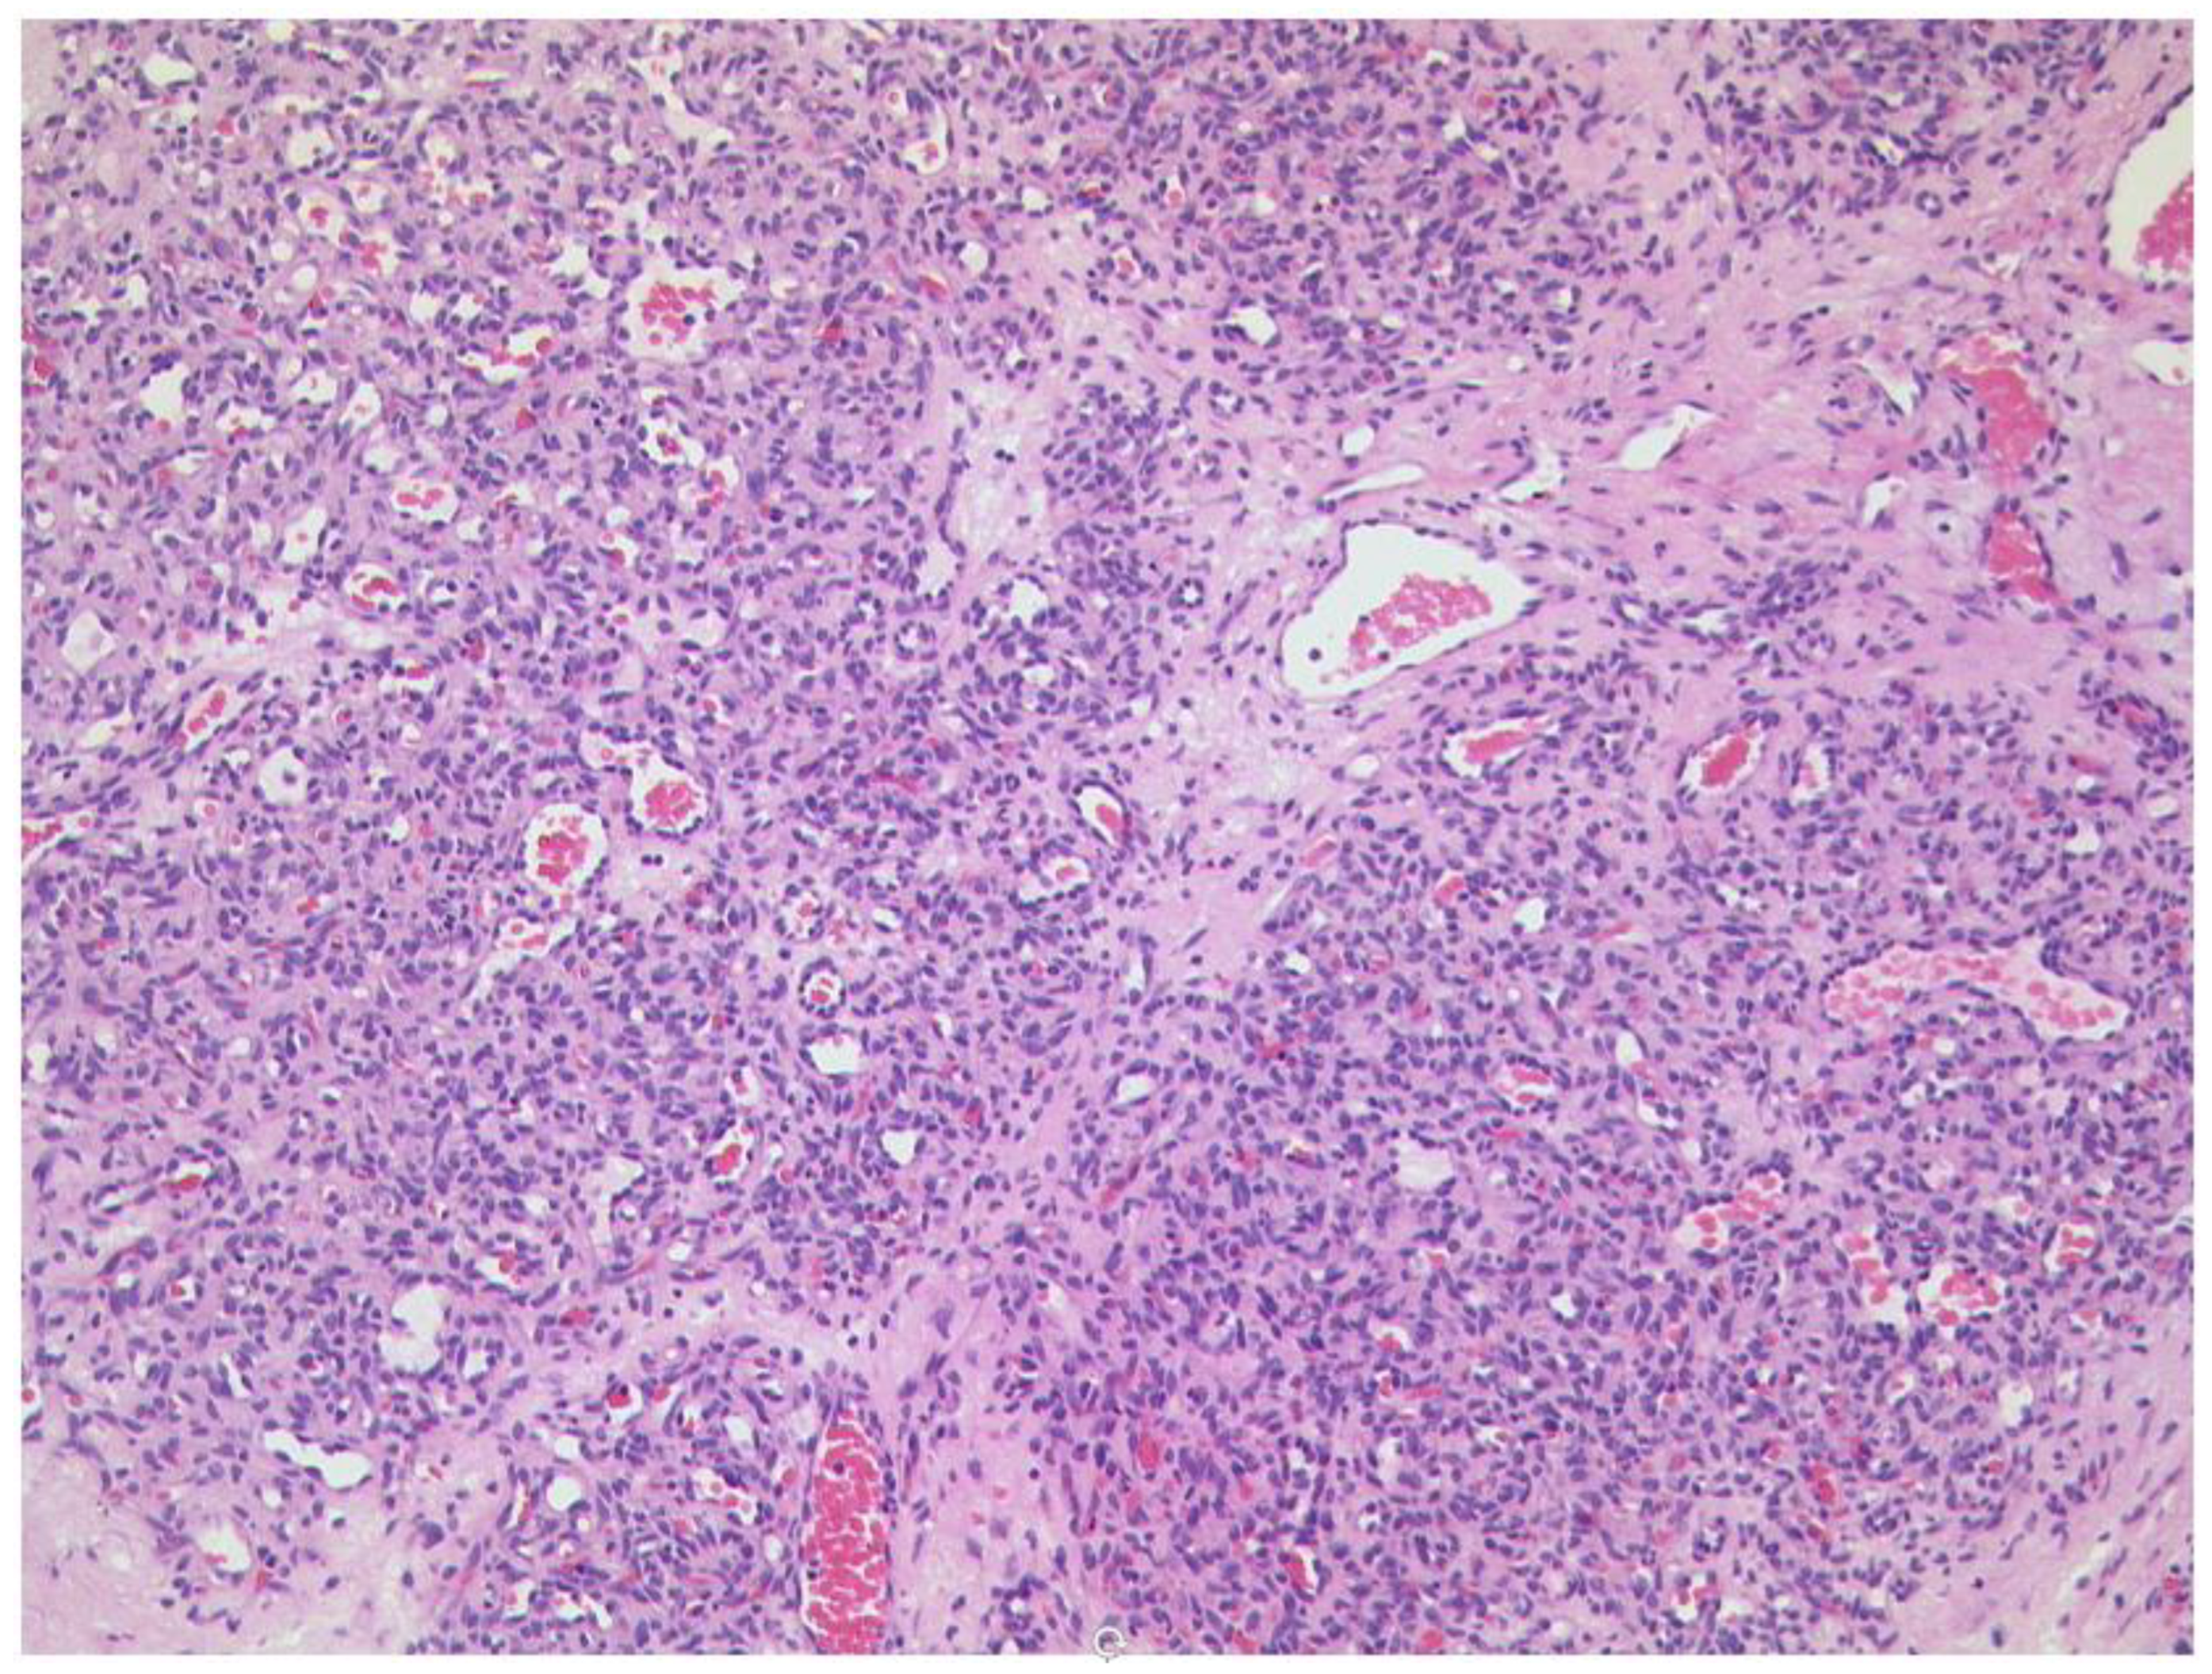

3.6.2. Rhabdomyosarcoma